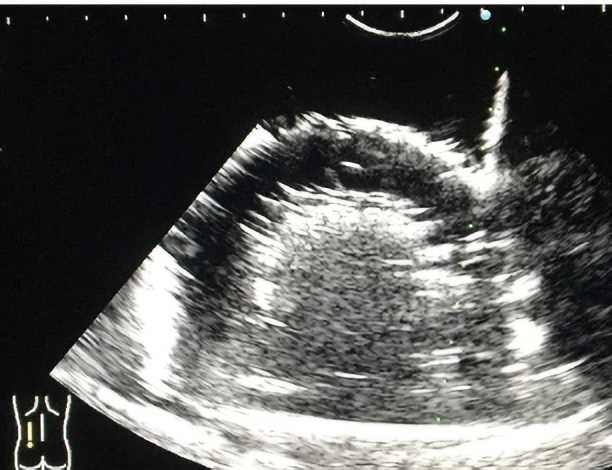

作製したモデルは、超音波下で腎臓の皮質・髄質に該当する部分のコントラストは実際の腎臓のものに類似しており、針穿刺の際にモデル内に針が侵入する様子が超音波下で観察可能です。本モデルの検証のため、岡山大学病院の腎生検経験20例未満の研修生10名に腎生検模擬を実施し、腎生検経験20例以上の腎生検に熟達した腎臓内科医20名がその様子を観察あるいは模擬を実施しました。また、腎生検模擬後に全参加者にアンケート調査を実施しました。その結果、90%の研修生が今回の腎生検模擬によって患者への腎生検に対する不安が軽減されると回答しました。

軟質エラストマー成型品/腎生検シミュレーター (製品名:JIN戦士君)